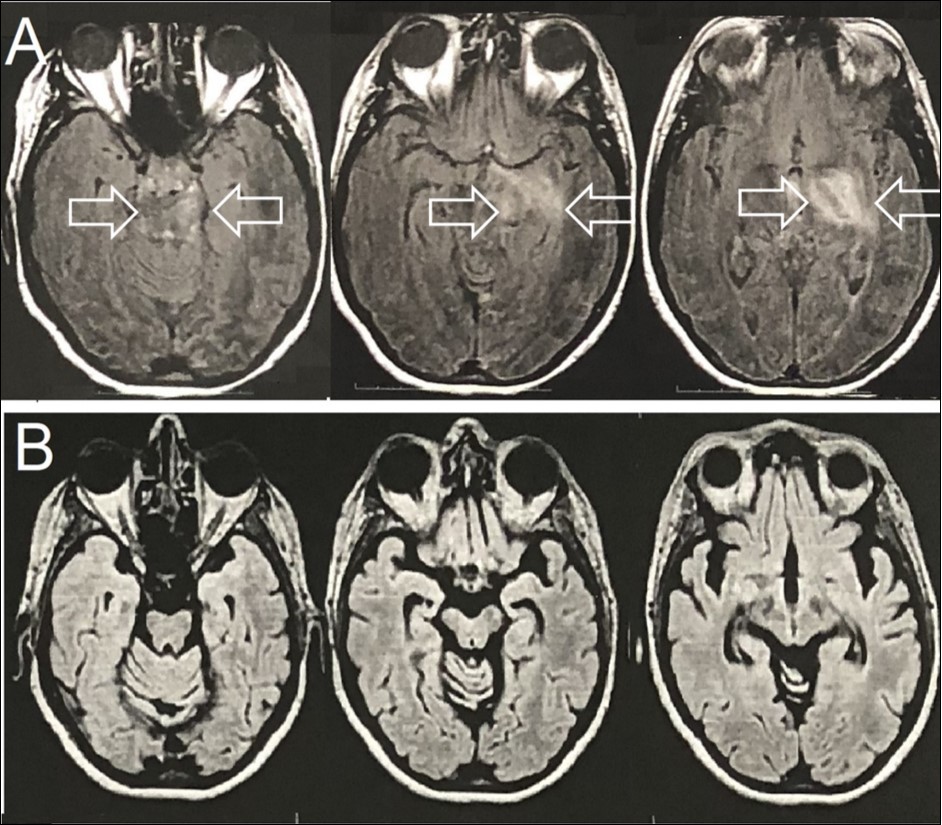

Family medical background was unremarkable. Brain T2-FLAIR magnetic resonance imaging (MRI) showed an expansive mass lesion at the left capsular nucleus region, with mesencephalic extension (Figure 1A). Cerebrospinal fluid analyses showed 15 cells, all of them lympho-monocytes, and protein of 45mg/dL (lumbar puncture). All other tests on spinal fluid were normal.

The patient was also referred to a neurosurgery department, where a brain biopsy was planned for diagnostic clarification. Meanwhile, the possible clinical diagnosis of BD was postulated and started treatment with 1 gram of methylprednisolone intravenously and for a period of 5 days with satisfactory results. Neurosurgery was then discarded. Therapeutic follow-up was instituted with azathioprine and after 2 months of treatment, due to abnormal liver function, anti-TNF-alpha (Infliximab) was was administered at 0, 2nd and 6th weeks and then every eight weeks; Despite cerebral atrophy, stable neurological evolution was found after 18 months of anti-TNF-alpha therapy (Figure 1B).

Figure 1.Brain Axial-FLAIR-MRI- (A) Expansive mass lesion with hyperintense signal in the left capsular nucleus region, with mesencephalic extension and enhancement by the paramagnetic agent (white arrows). (B) Complete improvement of the expansive mass lesion with the presence of brain atrophy.